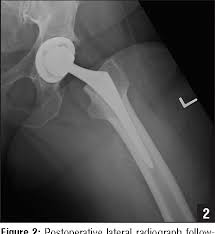

PINNACLE Hip Solutions is a modular cup system designed with a wide range of acetabular cup options biological and mechanical fixation alternatives and advanced bearing technologies that allows surgeons the flexibility to choose intraoperatively from among the most advanced technologies available depending on their patients individual needs.

Pinnacle Acetabular Cup System hip implants in configurations other than the metal-on-metal configuration can be remanded to their transferor districts in advance of the other centralized actions. The Pinnacle Acetabular Cup System our third generation modular design has been developed to take. The DePuy Pinnacle Acetabular Cup System which is used in total hip replacements is manufactured and sold by DePuy Orthopaedics a subsidiary of Johnson Johnson. The Pinnacle Cup System is one of the most widely used and clinically successful modular acetabular systems for hip replacement and will continue to be offered with both medical grade plastic and ceramic liners. Now potentially better bearing surfaces have become available. Depuy orthopaedics inc us pinnacle 100 acet cup 58mm pinnacle hip system. A wear analysis at the interface of the articulating surfaces of the. The Pinnacle Acetabular Cup System is uniquely designed with a range of acetabular cup options biological and mechanical fixationalternatives and advanced bearing technologies which provide you the power to choose the precise combination that best meets the individual needs of each patient. Evidence about the Depuy Pinnacle Acetabular Cup System - Independent Reviews by Clinicians for Clinicians.